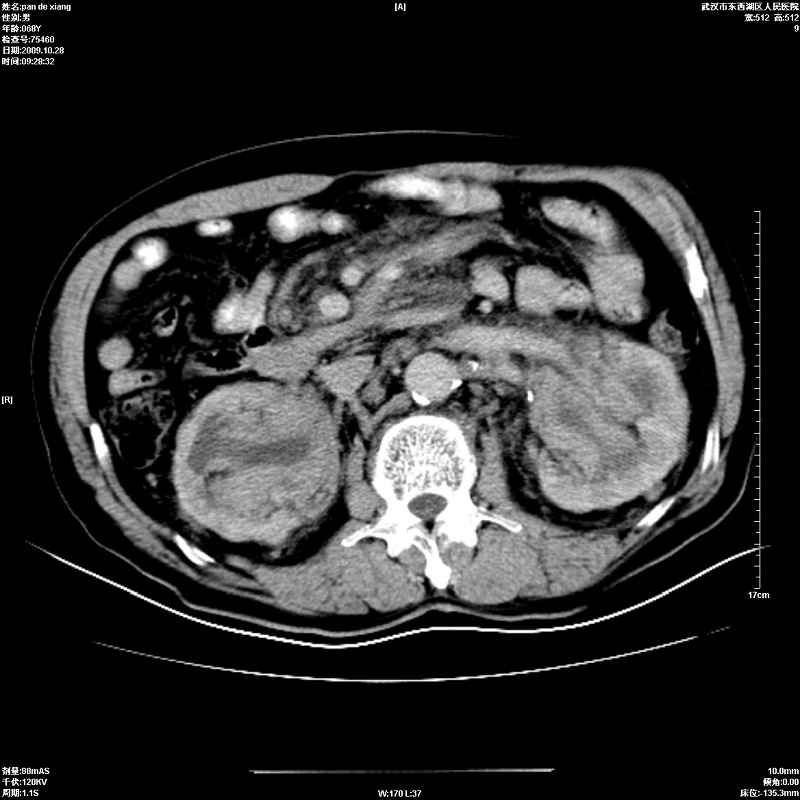

以下是引用杀毒软件在2009-10-28 20:41:00的发言:[br]结合临床考虑---白血病双肾改变或淋巴瘤。

以下是引用zxl51642在2009-10-29 9:59:00的发言:[br]结合临床“单克隆免疫球蛋白血症”,考虑双肾为继发损害并肾功能不全(尿中大量igg及少量iga、igm等大分子免疫球蛋白滤出所致继发损害),椎前软组织肿块为髓外造血。与浆细胞瘤有区别,平扫时有战友说的很清楚。